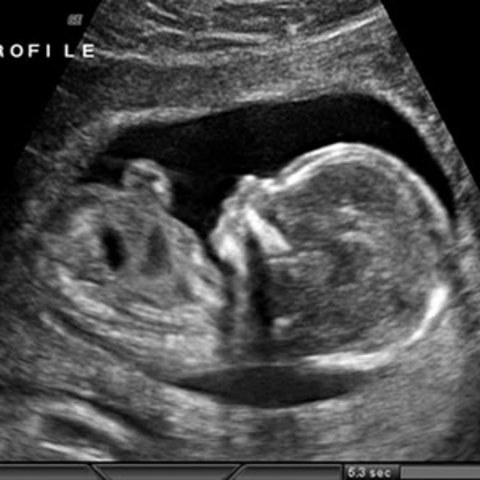

• Weeks 7-12

Weeks 7-12

Weeks 7-12 are when the baby's head develops and the eyes are beginning to be visible, baby's toes form, neck develops, genitals develop, and fingernails develop. Baby's will also develop a sense of smell in the weeks of 11-15. By the end of this week the baby is as big as a 2 1/2 inches and weighs 1/2 ounce.